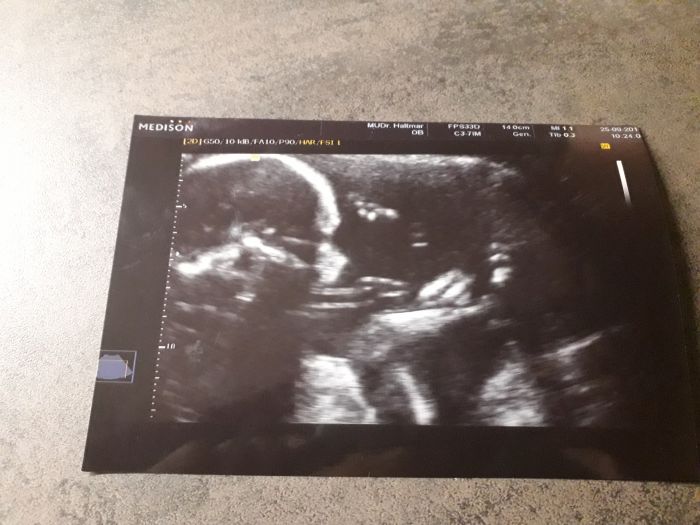

Andri jojo, byli jsme už minulý týden v úterý..Všechno v pořádku,mimčo odpovídá tabulkám, teď bude mít tak okolo 350g a cca 28cm

akorát je to teda extra stydlivý dítě, kolena má fakt až u brady a nohy od sebe prostě nedá a nedá

takže můj dr si vůbec nechtěl tipovat pohlaví, na FECHO screeningu byl dr taky bezradnej, pak prý se mu mimčo na půl vteřiny ukázalo trošku líp,tak říkal holčičku, ale že ruku do ohně za to nedá

tak na definitivní potvrzení si musím ještě počkat..příští týden začínám šestý měsíc, letí to jak blázen

Zkusím vložit fotku, tam je hezky vidět, kde až má strčený ty nohy